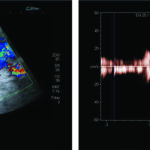

El DC permite una evaluación más exhaustiva, con la cual no solo podemos determinar con precisión los límites de la dilatación aneurismática sino que también hace posible percibir la turbulencia en el flujo dentro de la misma (Fig. 28).